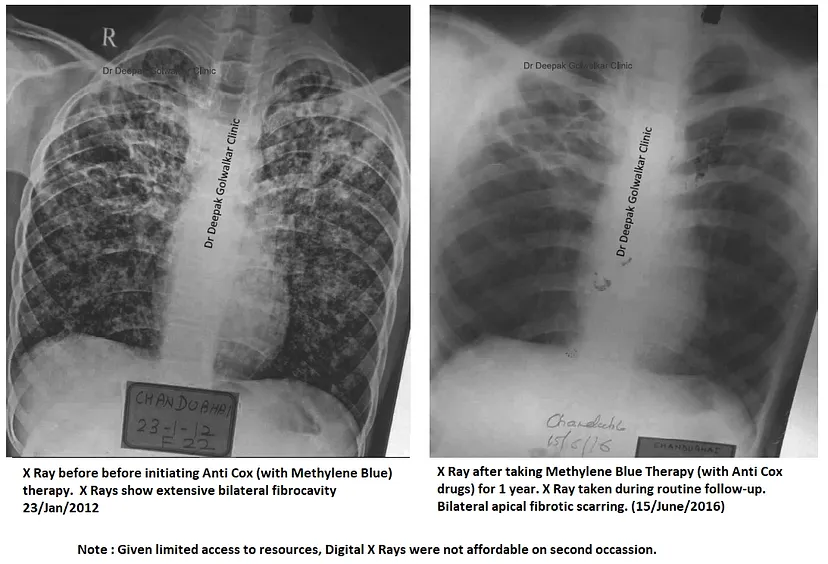

Dawkowanie błękitu metylenowego dr Golwalkarsa dla pacjentów i profilaktyki

https://1-dr--deepak--golwalkar-medium- ... _hist=trueDawkowanie błękitu metylenowego dr Golwalkarsa dla pacjentów i profilaktyki